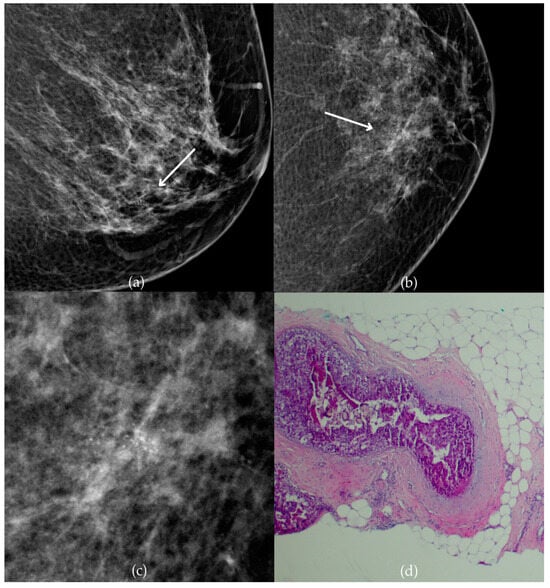

Mammogram and histopathological images (Figure 10) of a 66-year-old patient’s right breast show architectural distortion with associated fine pleomorphic calcifications of segmental distribution in the upper outer quadrant, corresponding to a BI-RADS 3 finding. Tissue analysis obtained through biopsy reported an intraductal papillary lesion without epithelial atypia (category B3). The patient underwent an excisional biopsy (quadrantectomy), and postoperative pathology confirmed the absence of carcinoma. One year after the initial diagnosis, the most recent US follow-up was classified as BI-RADS 2, confirming benign findings.

Figure 10.

Intraductal papillary lesion without epithelial atypia. (a) Mediolateral oblique (MLO) view; (b) craniocaudal (CC) view of the right breast showing architectural distortion with associated fine pleomorphic calcifications of segmental distribution (marked with arrows) in the upper outer quadrant. (c) Magnified mammographic image of fine pleomorphic calcifications of segmental distribution. (d) The histopathological image of the biopsy sample shows an intraductal papillary lesion without epithelial atypia (HE staining; 40× magnification).